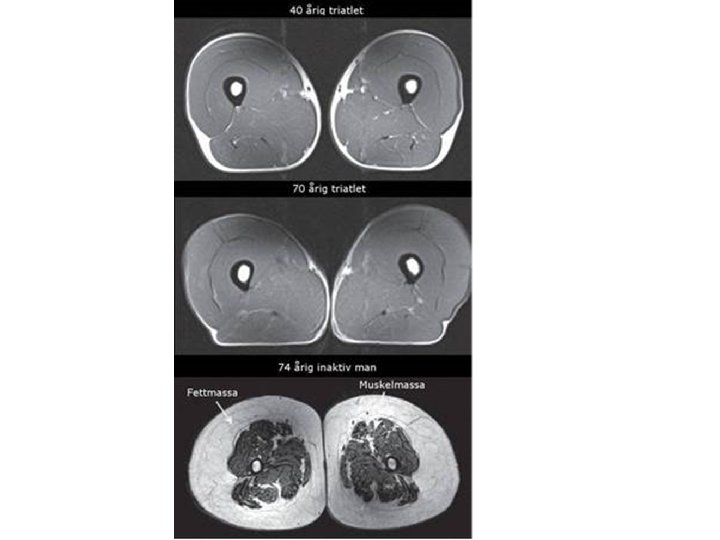

Bromsa åldrandet Ungdomens källa är fysisk aktivitet ”Muskulatur är den enskilt viktigaste faktorn med störst betydelse för äldres rörelsefrihet” (Rosenberg) • Sarkopeni= kombination av brist på muskulatur och nedsatt muskelstyrka • 50 -66 % av muskelns åldrande beror på inaktivitet

Sarkopeni • 1 % av din muskelmassa förvinner per år > 40 års ålder • > 70 års ålder snabbare sarkopeni • Främst de snabba muskelfibrerna som förtvinar först